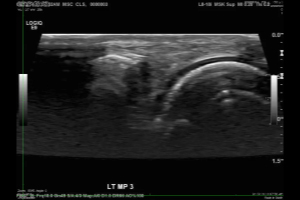

Using a small transducer, a sonographer recorded video images of 400 MPJs, as participants attempted to crack their knuckles. The sonographer also captured static images of each MPJ before and after participants tried their hands at cracking.

Two radiologists interpreted the ultrasound images, looking for sonographic evidence that would correlate with the audible cracks, which occurred in 62 of the 400 joints imaged.

"What we saw was a bright flash on ultrasound, like a firework exploding in the joint," Dr. Boutin said. "It was quite an unexpected finding."

Using the flashes on the ultrasound images, the radiologists were able to identify the joints with audible cracks with at least 94 percent specificity.

"There have been several theories over the years and a fair amount of controversy about what's happening in the joint when it cracks," Dr. Boutin said. "We're confident that the cracking sound and bright flash on ultrasound are related to the dynamic changes in pressure associated with a gas bubble in the joint." As for which comes first — the cracking sound or the flash of light — Dr. Boutin said that more research is needed.